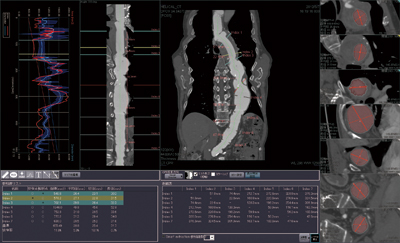

[ziostation2を利用して術前の大動脈計測を行う]

新病院では、3つの血管撮影室、ハイブリッドOR室にziostation2のフル機能クライアント端末(VGR)が設置されており、術前に作成した3D画像を確認しながら手技が行えるようになっている。

同院では、ステントグラフト術前の動脈瘤の計測に、ziostation2を活用しており、西村部長が自らziostation2を使って3D画像の作成と計測を行っている。計測には、標準搭載の3D解析の血管計測機能を用いて、3D画像を作成し目的の血管のパスを抽出させ、任意の2点間の距離や短軸MPR画像上で血管径の計測を行う。西村部長は、「ステントグラフト治療では、術前に動脈瘤の大きさや血管径を把握して、適切なステントグラフトを準備することが必要です。術前には詳細な3D画像は必要なく、血管と瘤のイメージが把握できる画像が素早く得られることが大切ですが、ziostation2では再構成画像がほとんど一瞬で表示され、計測も簡単に行えます」と使い勝手を評価する。

■ ziostation2によるステントグラフト術前血管計測

![]() ziostation2の3D解析による血管計測 |

![]() 胸部大動脈瘤症例の3D再構成画像 |